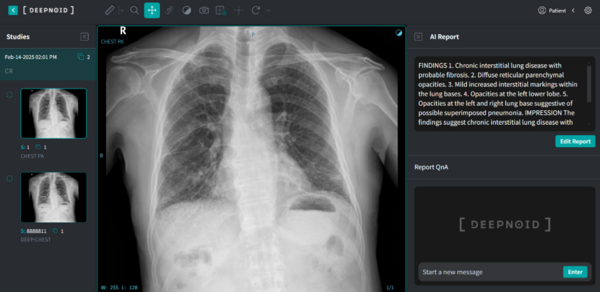

루닛에 앞서 딥노이드도 생성형 AI 기반 흉부 엑스레이 판독 솔루션 ‘M4CXR’ 개발에 착수하며 시장 경쟁에 뛰어들었다.

M4CXR은 X-ray 영상을 분석해 정상 소견을 포함한 41개 이상 흉부 질환 관련 소견에 대해 수초 내 판독 리포트 초안을 생성하는 기능을 갖췄다. 지난 8월 식품의약품안전처로부터 임상시험계획(IND)을 승인받아 현재 임상시험을 진행 중이며, 인허가 절차도 병행되고 있다.

해당 제품은 최근 식약처로부터 혁신의료기기로 지정됐다. 혁신의료기기는 기술집약도와 개선 가능성이 높은 제품에 부여된다. 지정 기기는 ‘의료기기산업 육성 및 혁신의료기기 지원법’에 따라 인허가 과정에서 맞춤형 기술 상담과 우선 심사 등의 혜택을 받을 수 있다.

딥노이드는 향후 CT, MRI 등 다양한 영상 모달리티와 뇌·폐 질환 영역까지 리포트 자동화 기능을 확장할 계획이며, 과학기술정보통신부가 주관하는 ‘초거대 생성형 AI 개발사업’ 의료 특화 부문 주관기관으로 참여해 멀티모달 AI 플랫폼 구축도 병행하고 있다.